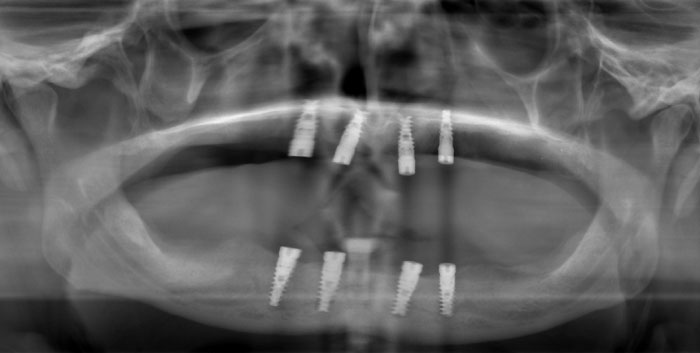

Stegprothesen auf Zahnimplantaten

Die Prothesen werden auf dem Steg (ihrer Verankerung) aufgeklickt. Die Prothese wird dadurch stabiler und belastbarer in Bezug auf die aus unterschiedlichen Richtungen kommenden Kaukräfte. Diese Lösung eignet sich besonders dann gut, wenn das Volumen des Knochenkamms das Setzen von noch mehr Implantaten zum Verbauen einer festen Brücke nicht zulässt.

Die Zahnimplantate werden durch eine Metallstegkonstruktion miteinander verbunden. Nach dem gleichen Prinzip, wie bei auf natürlichen Zähnen befestigten Prothesen, klicken sich bei einem auf Implantaten befestigten Zahnersatz die Präzisionsaufsätze aus Teflon in den Steg ein.

Die Prothese sitzt somit fest, ohne sich lösen zu können. Der Patient erlangt mit einer Stegprothese auf Zahnimplantaten 100% der Funktionalität und Ästhetik seiner Zähne wieder.